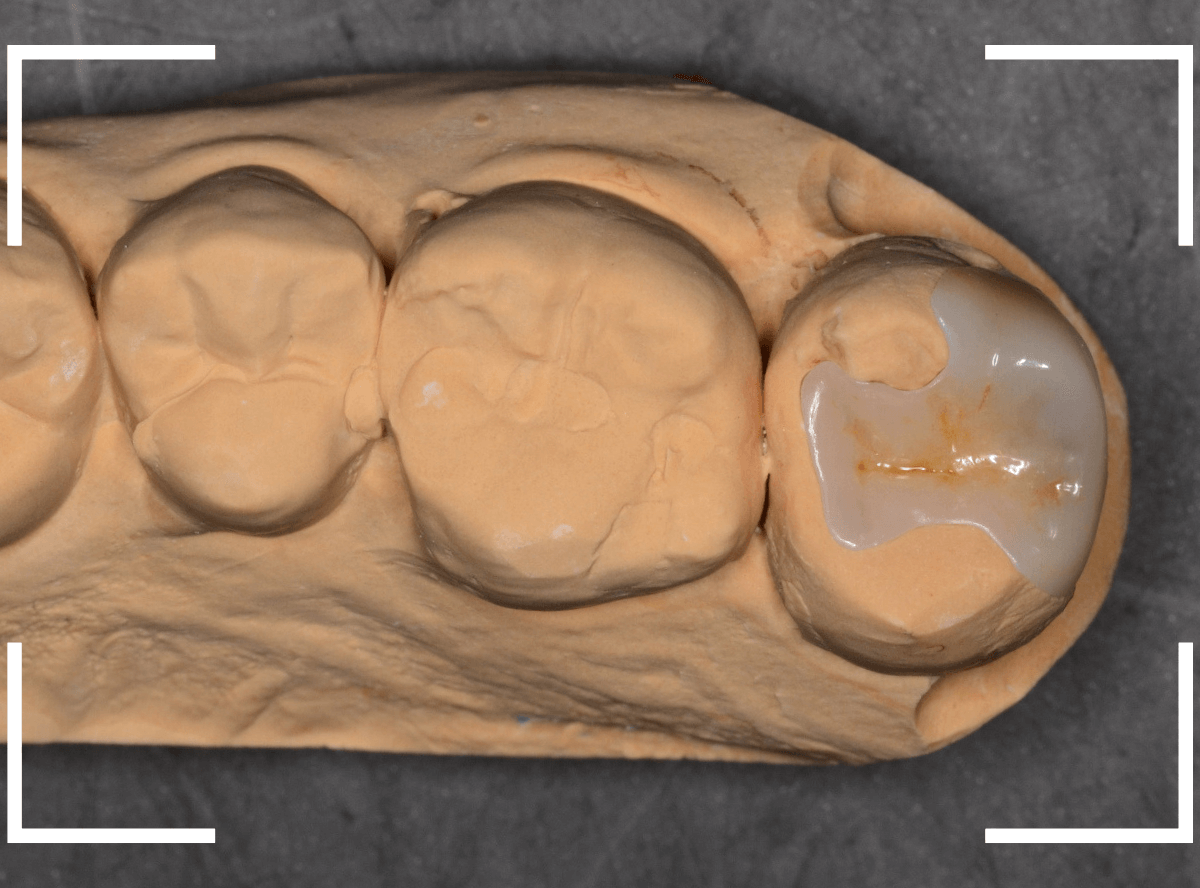

Case.5 上の一番奥の部分が深い虫歯!2

こちらも上の奥歯の奥側が虫歯になってしまった患者さんです。

本人に自覚症状はないようですが、一見して虫歯が大きそうだな、と思いました(><)

青い線が歯の神経、赤い線が虫歯です。

以前にレジン治療をした中で虫歯が進行してしまい、かなり神経に近くなってしまっていると思われます。

さて、しばらく経過観察した後、症状もありませんでしたので、型どりをして最終修復に入ります。

「良い素材で治療をしたい」という患者さんのご希望でしたので、ジルコニア・インレーで治療をする事になりました。

模型上で精密に製作します。

set後の写真です。

なんとか審美性も確保した状態で治療を終われました。